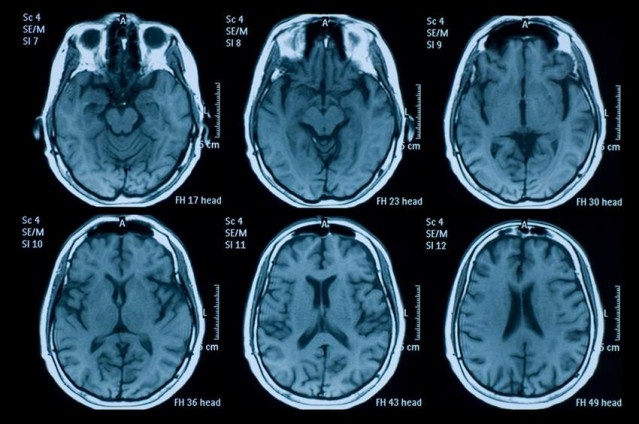

Un equipo de investigadores internacionales liderados por la compañía Aivocode, una 'spin-off' del institudo Sanford Burnham Prebys de San Diego (Estados Unidos), ha identificado un "significativo" efecto neuroprotector del compuesto CAQK en modelos de ratón y cerdo de traumatismo craneoencefálico.

El estudio, publicado en la revista 'EMBO Molecular Medicine', ha mostrado como este péptido formado por cuatro aminoácidos se dirige específicamente a las zonas dañadas del cerebro tras ser inyectado por vía intravenosa poco después de la lesión, "atraído" por las glicoproteínas, que están presente en mayor cantidad en las zonas lesionadas tras un traumatismo.

CAQK se acumula en las zonas marcadas por la proteína y logra reducir tanto la inflamación como la muerte celular y el daño en el tejido cerebral, mejorando también la recuperación funcional, sin mostrar toxicidad aparente en ratones, lo que abre "nuevas posibilidades" a tratar zonas lesionadas del cerebro.